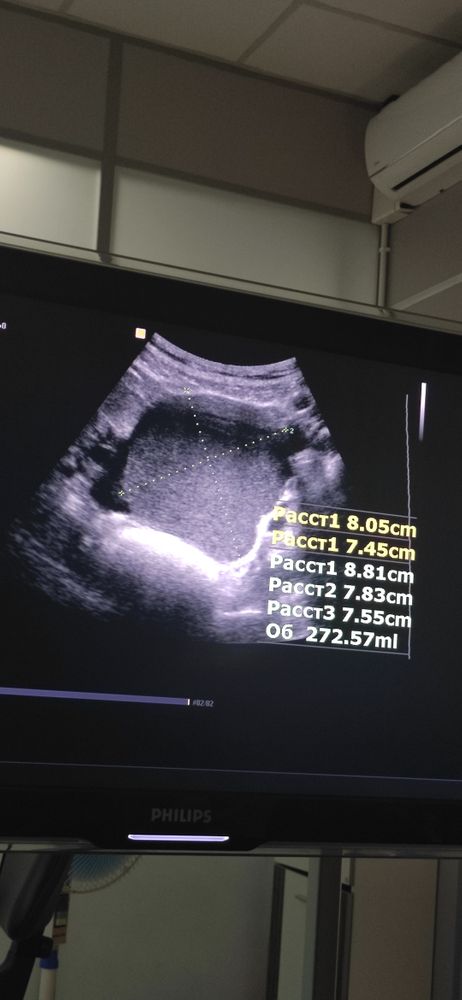

Не хочу вас кошмарить , но чем дольше вы будете с эндометриомами, тем больше тканей яичника они уничтожат . Вырастили мне по халатности вот такое чудовище, от левого яичника почти ничего не осталось ... Как итог, он не работает больше(